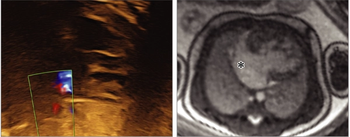

A 43-year-old male presents for suspected PE evaluation. What is the diagnosis?